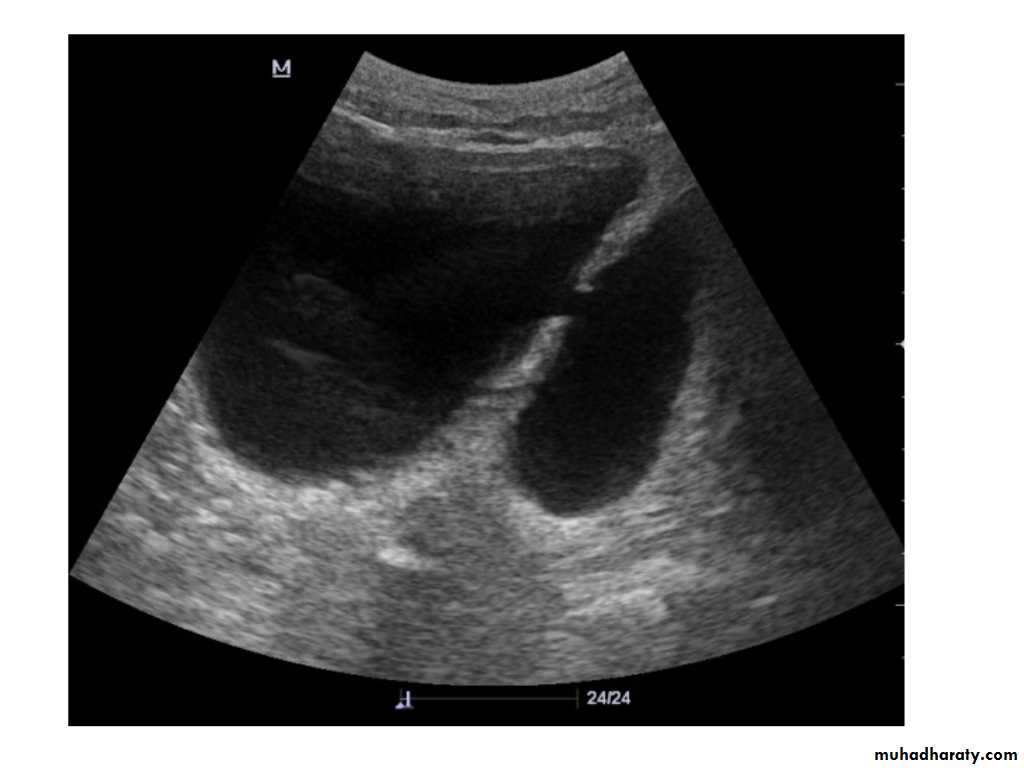

IVU shows

1. The kidneys at low position .2.Close to the spine with long axis parallel to the spine

3. Malrotation manifested by medially directed calyces.

4- The renal pelvis and ureters are anterior and lateral in position.

5- Hydronephrosis and calculi highly associated.